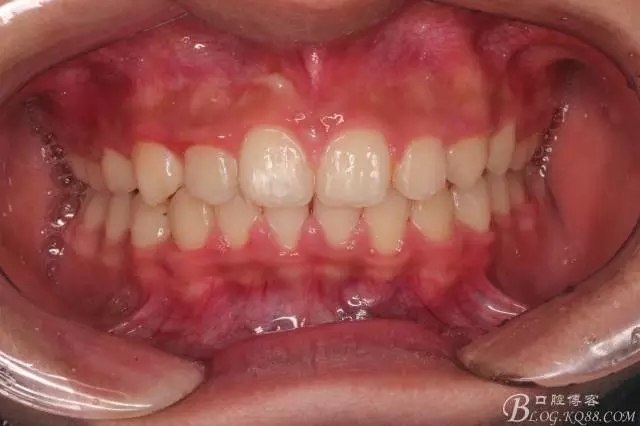

一晃快兩年了,我覺得關(guān)節(jié)重建及咬合穩(wěn)定,再加上患者的急迫愿望,我們拆除了矯正器。

尖牙關(guān)系中性,磨牙關(guān)系中性,咬合鎖結(jié)良好!